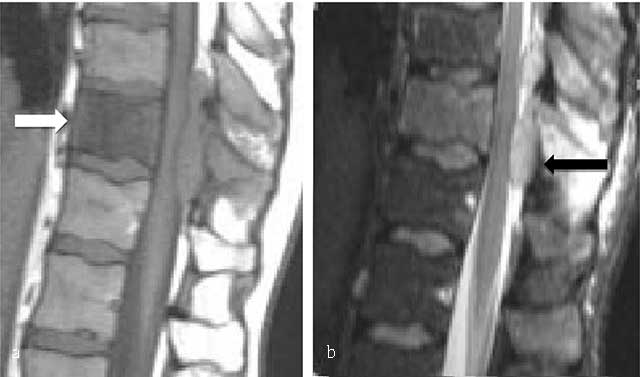

Figure 8

B-cell lymphoma of L2. MR: (a) Sagittal T1- and (b) T2-WI image show an osseous lesion of L2 (white arrow) extending into spinous process of L1 and L2 and in the posterior epidural spaces (black arrow) but without extension through the intervertebral disk.